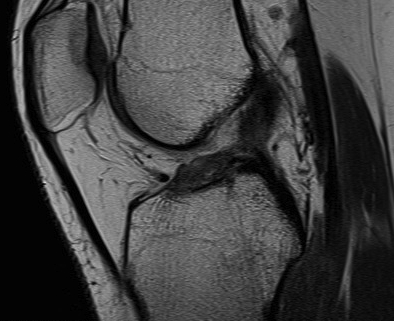

Torn ACL on MRI

Findings

- high signal intensity / oedema in ACL, especially acutely

- unable to identify continuous fibres from tibia to femur

- loss of taut, straight line of fibres

Sagittal T2 MRI with midsubstance ACL tear Sagittal T1 MRI with midsubtance ACL tear

Sagittal MRI with complete ACL rupture